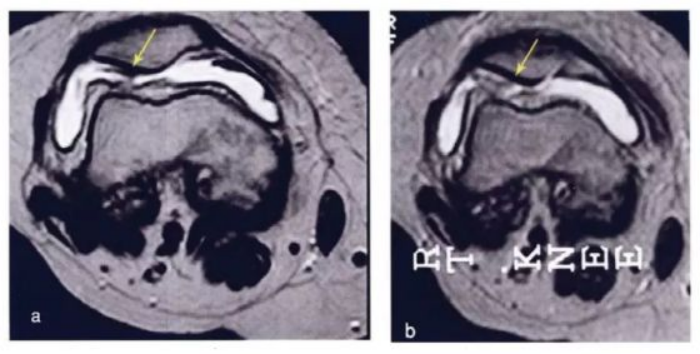

下图是治疗前后的核磁对比,,,如之前的一样,,,,颜色越蓝,,,代表软骨质量越好。。可以看出间充质干细胞治疗后软骨质量明显提高。。

下图所示,,颜色越红代表软骨质量越差。。。。可以看出治疗前(左边)的软骨大部分是黄色,,治疗后蓝色明显偏多,,,表示间充质干细胞治疗后软骨质量增加。。